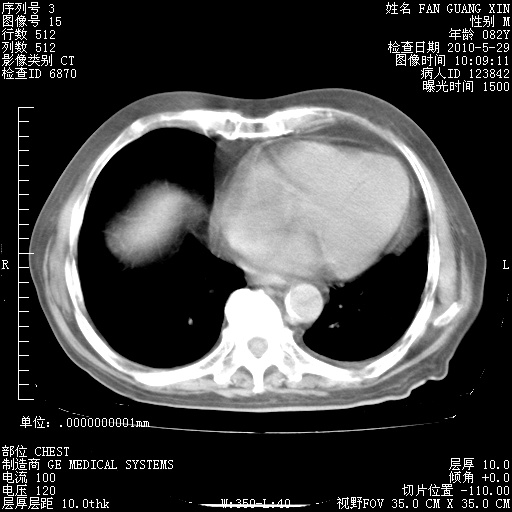

治疗3周后的肺部CT纵隔窗

从胸部影像学来看,的确有好转。至于目前为何发热不甚清楚?除了发热还有其他症状如有无喀痰,痰呈丝状吗?等等。尽量搜寻有无致发热其它可能原因?真菌?其它?如果的确无其他致发热的原因,考虑将甲强龙调至60-80mg bid/日。免疫全套基本无异常,考虑多系特发性肺间质纤维化

阅读此次胸部CT,肺间质渗出性改变较入院时有吸收。目前从体温、白细胞、中性分叶明显增高,肯定存在细菌感染(发生医院感染哦,若无消化道及泌尿系统等感染的依据,肺部感染可能大)。若你院头孢哌酮舒巴坦钠耐药率较高,同意你的方案,若48小时体温仍高,可考虑使用碳青霉稀类抗菌药物,同时可予超声雾化、注意滴数时加大液体量。白蛋白33.30g/L较低哦,需加强营养等支持治疗。